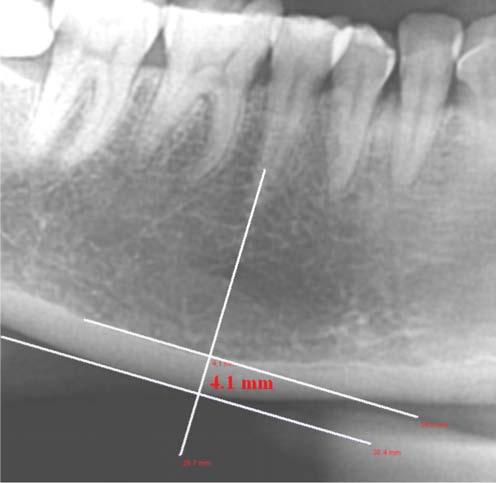

The purpose of this study was to obtain the description of the mandibular bone quality of male and female patients between 40-60 years old and their differences based on mandibular cortical bone thickness measured using Mental Index (MI).

Forty digital panoramic radiographs, which consisted of twenty male and twenty female patients, 40-60 years old, were observed. Mandibular cortical bone thickness was measured using MI on both sides of the mandible. The average MI score of two groups were then assessed using t-sample independent test.

There were significant differences of mandibular bone quality based on mandibular cortical bone thickness measurement using MI between male and female patients (p<0.05).

Mandibular bone quality based on cortical bone thickness measurement using MI of male and female patients indicated a significant difference.